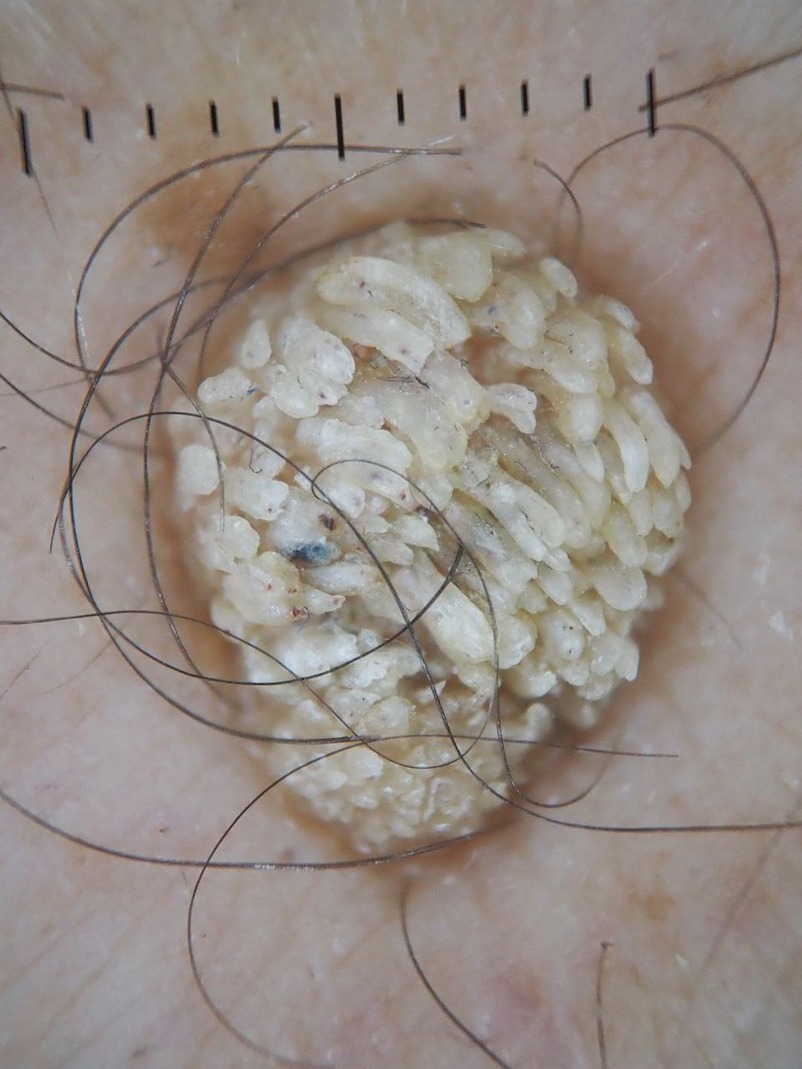

Paramount Skin Check offers professional, in-person skin assessments using advanced imaging technology to detect early signs of skin cancer and other skin conditions.

Each case is reviewed by a fully licensed consultant dermatologist, ensuring that your results are based on expert clinical judgment—not just algorithms.

we believe that early detection requires the eyes and experience of real specialists who understand the subtle warning signs that machines may miss. Within 48 hours,